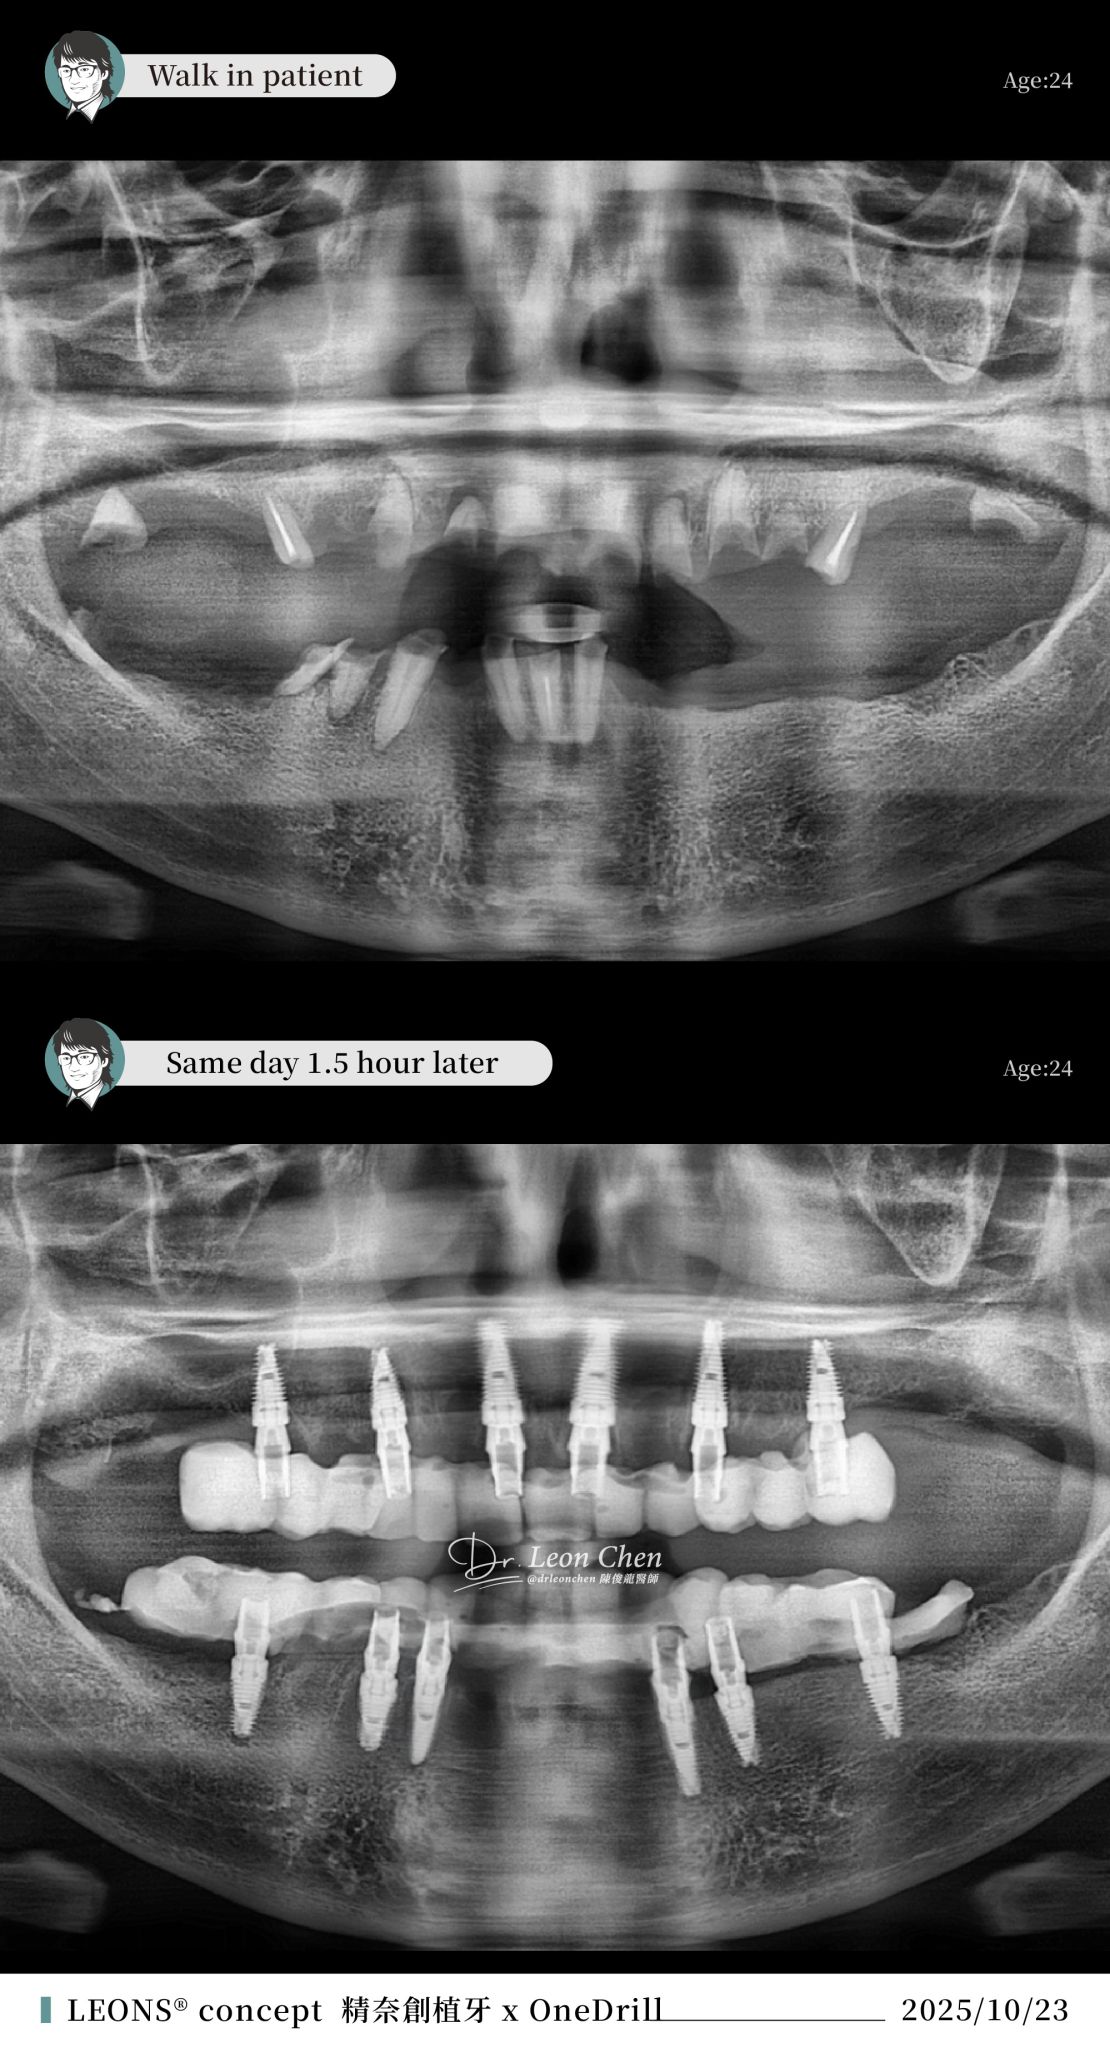

精奈創一鑽植牙系統團隊|從一口爛牙到重新微笑

一位新病人帶著滿口爛牙走進診所,在陳博士全口植牙後,當天「走進來一口爛牙、走出去就有全口牙」,可以正常飲食,完全不影響生活品質。

這位年輕病人經濟條件有限,因此採取最保守的六根植體的全口重建。這個方案更難做,要在沒有導板的情況下,還要保持完美地平行,展現出極高的臨床技術水準。

而且這個設計「進可攻、退可守」,未來若要再追加植體,也能輕鬆完成。

相較於初診時的狀況,病人現在已經非常滿意。

不要為了微小的修飾,讓病人承受更多痛苦。「他才24歲,牙齒會拖成這樣,一定是害怕看牙。」能在最短時間讓病人重新開口笑,這就是博士所謂「照顧病人的身心靈」。